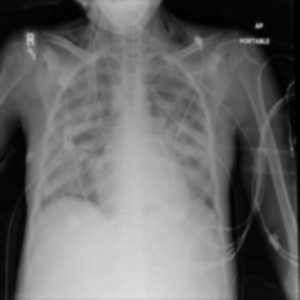

Filter natijalari

Gaussian Blur

CLAHE

Median

Threshold